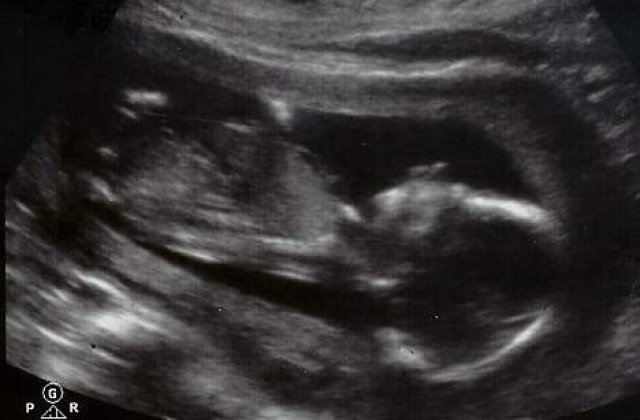

Cuplul din Minneapolis a incarcat, in mod regular, ecografii ale fatului, care este, potrivit doctorilor, in stare perfecta de dezvoltare. Medicii le-au confirmat cuplului ca asteapta un baiat, pe care acestia l-au poreclit 'Wiggles'.

Alisha se afla acum in cea de-a 17 saptamana de sarcina, iar utilizatorii site-ului au timp pana pe 7 decembrie pentru a decide daca micutul “Wiggles” “merita sau nu sa traiasca”. Data de 7 decembrie este stabilita exact cu doua zile inainte de limita de 20 de saptamani, termenul legal pana la care o femeie poate sa faca avort in Statele Unite.